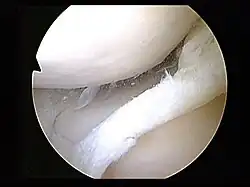

Surgery

Arthroscopy is a surgical technique in which a joint is operated on using an endoscopic camera as opposed to open surgery on the joint. The meniscus can either be repaired or completely removed.[20] Surgery is not appropriate for a degenerative meniscus tear, absent locking or catching of the knee, recurrent effusion or persistent pain.[25] Evidence suggests that it is no better than conservative management in those with and without osteoarthritis.[31][32] Surgery appears to offer no benefit to adults who have mild arthritis.[32]

An independent international guideline panel recommended against arthroscopy for degenerative meniscus tears; this conclusion derived from evidence of no lasting benefit and that less than 15% of patients experience even a short-term benefit.[31] Disadvantages include a two to six week recovery time and rare but serious adverse effects that can occur, including blood clots in the legs, surgical site infections, and nerve damage.[33][34][35] The BMJ Rapid Recommendation includes infographics and shared decision-making tools to facilitate a conversation between doctors and patients about the risks and benefits of arthroscopic surgery.[31]

If the injury is isolated, then the knee would be relatively stable. However, if an injury such as an anterior cruciate ligament injury (torn ACL) is coupled with a torn meniscus, then an arthroscopy is recommended. A meniscal repair has a higher success rate given an adequate blood supply to the peripheral rim.[36] The interior of the meniscus is avascular, but the blood supply can penetrate up to about 6 millimetres (0.24 in). Therefore, meniscus tears that occur near the peripheral rim are able to heal after a meniscal repair.[1] One study found that repair is better than removal (meniscectomy). The amount of rehabilitation time required for a repair is longer, but removing the meniscus can induce osteoarthritis. Meniscectomy rehab requires four to six weeks. Repair requires four to six months. If conservative treatment is ineffective, surgical intervention may be required. Younger patients are typically more resilient and respond well to this treatment, while older, more sedentary patients do not have a favorable outcome after a repair.[37]